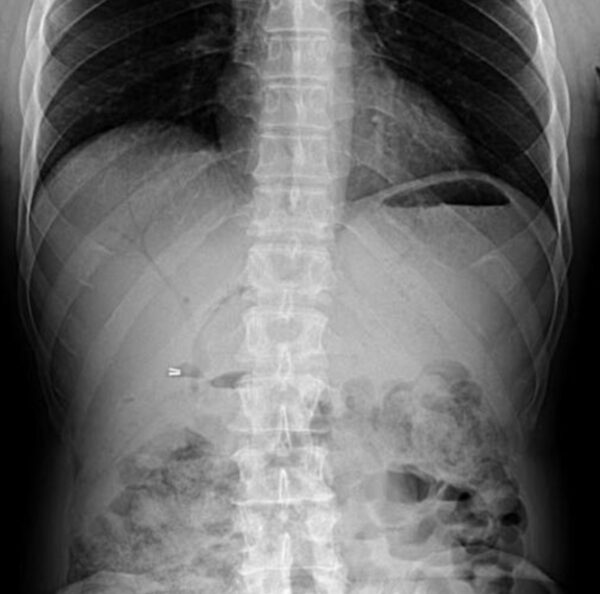

https://radiopaedia.org/cases/pneumobilia-1

X-RAY

GIT